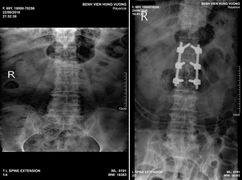

Bệnh viện Đa khoa Hùng Vương (Phú Thọ) vừa tiếp nhận chị B.T.H. (65 tuổi, ở Đoan Hùng, Phú Thọ) nhập viện trong tình trạng đau nhiều cột sống lưng và hạ vị.